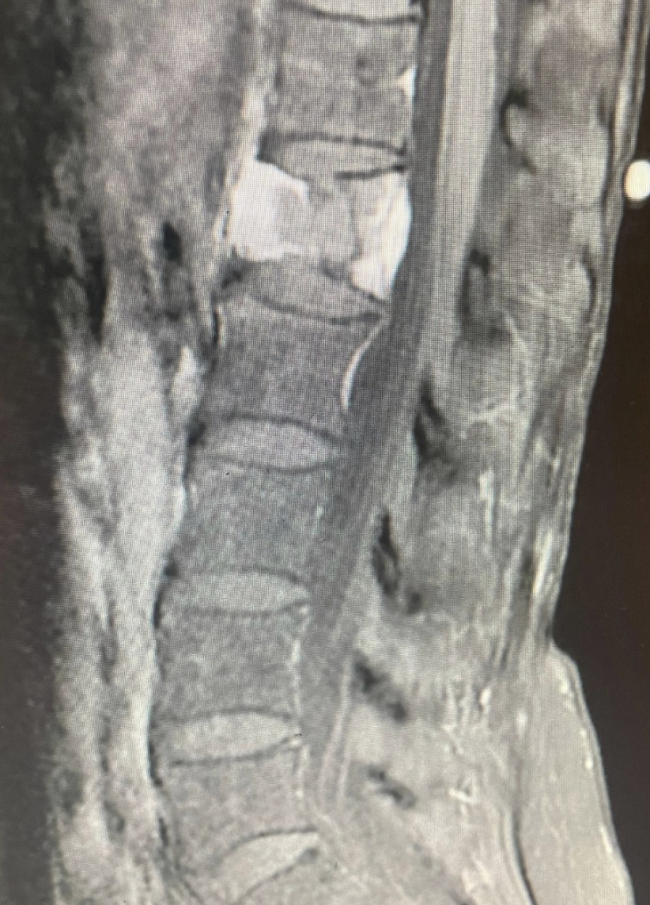

Cervical total disc replacement or disc arthroplasty is becoming an increasingly popular procedure. Now, the cervical disc replacements are even approved for doing 2 levels, as in this recent case that I performed. Is it right for you? Many things are possible in spine surgery but only a few things are most appropriate for you…